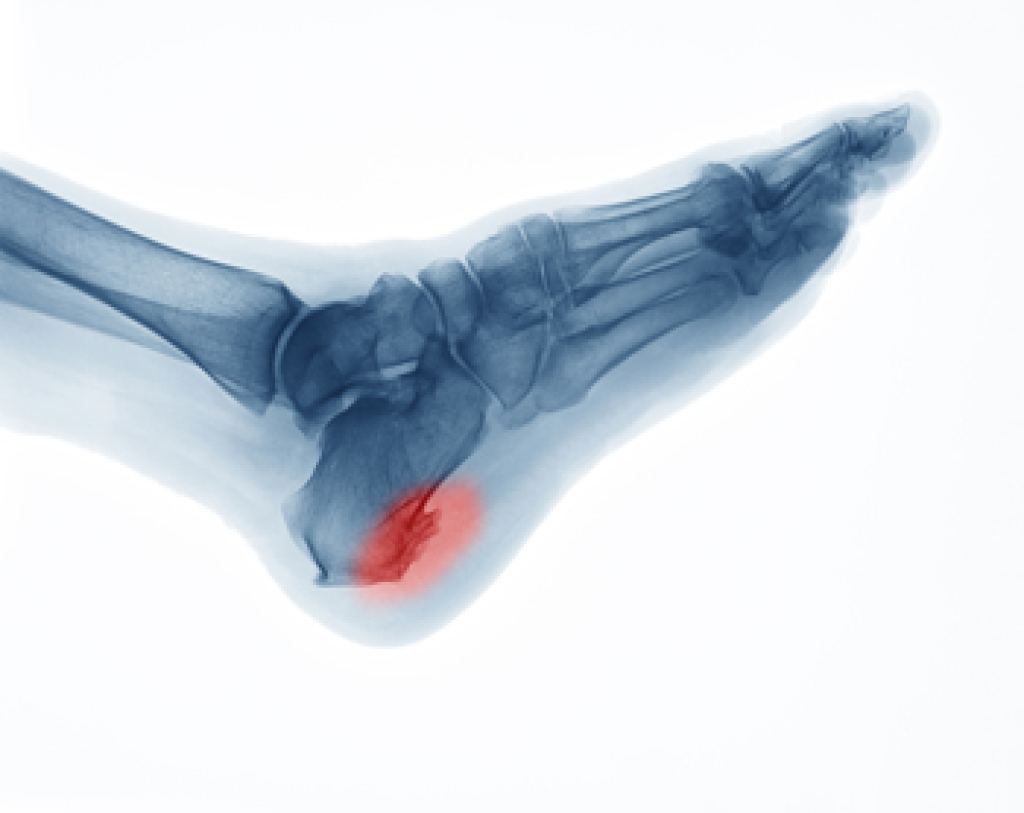

- Plantar fasciitis

Due to the wide variety of potential causes of ankle pain, podiatrists will utilize a number of different methods to properly diagnose ankle pain. This can include asking for personal and family medical histories and of any recent injuries. Further diagnosis may include sensation tests, a physical examination, and potentially x-rays or other imaging tests.